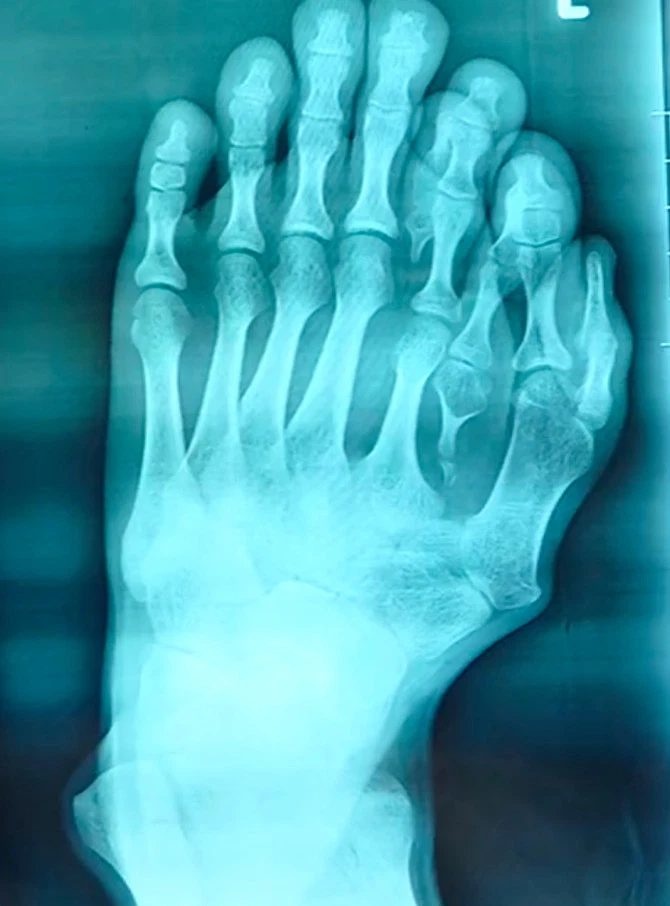

Dị tật của một thanh niên Trung Quốc có tới 14 ngón chân đã sống trong nhiều thập kỷ chỉ vì cha mẹ anh này nghĩ rằng đó là điềm báo may mắn, nhưng lại khiến chàng trai bị mọi người xung quanh kỳ thị đến mức phải ngừng đi dép từ năm 10 tuổi.

Bệnh nhân 21 tuổi có tên “Ajun”, sống tại Quảng Đông, Trung Quốc cho biết bốn ngón chân phụ trên bàn chân trái đã khiến anh bị mọi người xung quanh kỳ thị đến mức anh này phải ngừng đi dép từ năm 10 tuổi.

Cận cảnh bàn chân 14 ngón của anh Ajun

Ajun nói với các bác sĩ rằng cha mẹ anh biết rõ về tình trạng của con mình ngay khi anh được sinh ra. Tuy nhiên, thay vì làm phẫu thuật cắt bỏ ngón chân thừa cho con, cha mẹ anh lại tin lời khuyên của một thầy bói rằng ngón chân phụ của anh là 'một món quà từ thiên đàng' không nên cắt bỏ.

Bàn chân được chụp X-quang

Ajun cho hay: “Bố mẹ tôi rất mê tín, vì vậy họ đã không điều trị cho tôi. Họ nghĩ rằng, nếu các ngón chân thực sự trông quá tệ, tôi chỉ cần giấu chúng đi bằng cách đeo giày là xong”.